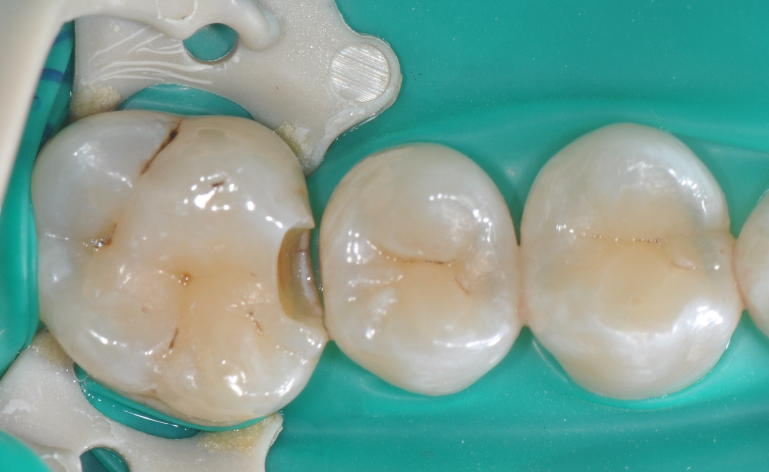

◆去腐完成之后

◆术后即刻照,如果邻面边缘出现悬突,可以使用12#手术刀去除,再配合抛光条抛光

◆术后撤离橡皮障后口内照片,术后1周复查,我们修正了边缘嵴的斜度及邻面轴线上的多余材料;复查是很重要的,能够发现第一次操作的时候遗留的不足,并且再次修正,保障了充填体的寿命。该案例也得益于改善了的成形片,修正了以往的成形片邻面龈缘区域材料残留形成过多的悬突材料,避免了术后龈乳头炎的发生!